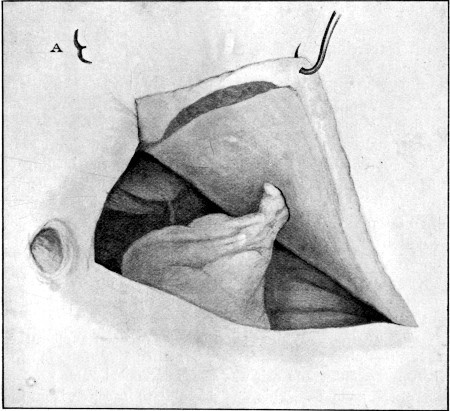

84. Subcutaneous Division of Abdominal Muscles409

85. Lateral Incomplete Wound of Small Intestine. Slit Form416

86. Lateral Perforation of Small Intestine. Gutter Form417

87. Entry and Exit Wounds in a Transverse Perforation of Intestine418

88. Inner Aspect of Piece of Intestine Shown in Fig. 87419

89. Impaction of Omentum in Exit Wound of Abdominal Wall421